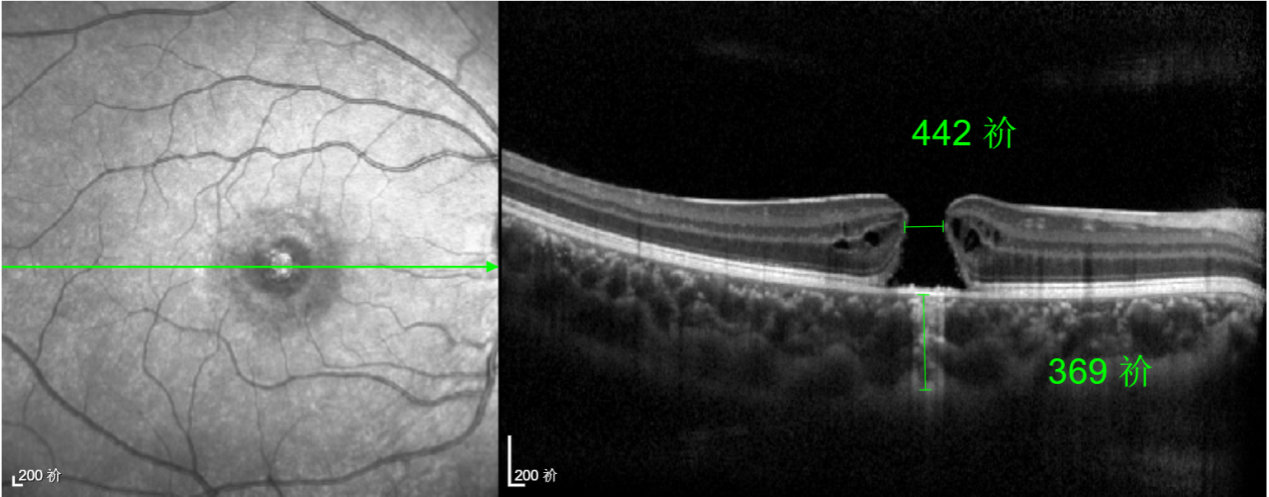

經(jīng)過(guò)詳細(xì)的檢查和評(píng)估,王曉波主任決定采用“內(nèi)界膜翻轉(zhuǎn)覆蓋聯(lián)合粘彈劑固定術(shù)”為誠(chéng)誠(chéng)進(jìn)行治療。

術(shù)中,醫(yī)生精細(xì)剝離黃斑區(qū)的內(nèi)界膜后,并非直接丟棄,而是巧妙地給它翻個(gè)面,讓它變成一塊天然“創(chuàng)可貼”,嚴(yán)密覆蓋在黃斑裂孔的表面。覆蓋的內(nèi)界膜像微型支架一樣撐住裂孔邊緣,防止它擴(kuò)大;同時(shí),這層膜本身含有能促進(jìn)生長(zhǎng)的“養(yǎng)分”,能顯著刺激裂孔周圍的視網(wǎng)膜組織像爬山虎一樣快速生長(zhǎng)、蔓延過(guò)來(lái),最終把裂孔“補(bǔ)”好。

除此之外,利用自體組織覆蓋為黃斑裂孔提供了理想的愈合環(huán)境,裂孔閉合速度顯著快于傳統(tǒng)方法。誠(chéng)誠(chéng)接受手術(shù)24小時(shí)后,檢查可見(jiàn)內(nèi)界膜瓣位置良好;術(shù)后1個(gè)月,黃斑裂孔已經(jīng)閉合,視力恢復(fù)到0.5;術(shù)后兩個(gè)月,視力進(jìn)一步提升到0.7。